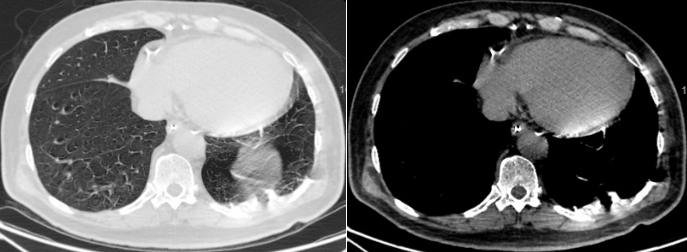

5月14日和5月20日复查胸片(图17)

17  复查胸片